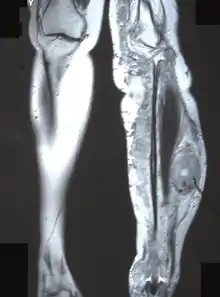

Malignant peripheral nerve sheath tumor. Back skin, 65-year-old man.

MPNST